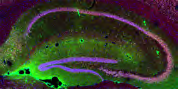

Molecular Psychiatry | 深圳先进院杨帆团队揭示压力应激导致焦虑与代谢异常的神经机制

揭示了慢性压力应激中下丘脑腹内侧核团(Ventromedial hypothalamus, VMH)神经元的簇状放电对焦虑及能量代谢的调控作用,而钙离子通道Cav3.1在上述调控中扮演了重要角色。

北京时间2022年3月22日,中国科学院深圳先进技术研究院脑认知与脑疾病研究所、深港脑科学创新研究院杨帆课题组在Nature旗下的神经科学领域著名期刊Molecular Psychiatry (IF 15.9)上发表题为“Cav3.1-driven bursting firing in ventromedial hypothalamic neurons exerts dual control o...